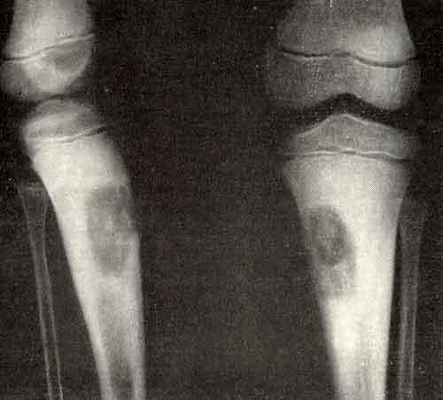

(Слева) Рентгенография в ПЗ проекции: умеренно агрессивный, вспученный литический диафизарный очаг с псевдотрабекуляцией и патологическим переломом в дистальном отделе. Данные признаки не специфичны. Двумя наиболее вероятными диагнозами являются неоссифицирующая фиброма и десмопластическая фиброма.

(Справа) МРТ, аксиальная проекция, режим Т1: внутрикостный очаг у этого же пациента В, характеризующийся сигналом, интенсивность которого немногим ниже сопряженной мышцы. Визуализируется выраженная вспученность малоберцовой кости. Такие признаки неспецифичны, однако сигнал очень низкой интенсивности предполагает наличие фиброзного очага. (Слева) МРТ, аксиальная проекция, режим Т2, с подавлением сигнала от жира: у этого же пациента определяется область преимущественно низкоинтенсивного сигнала, окруженная зоной умеренно выраженного отека. Низкоинтенсивный сигнал занимает большую часть патологического очага. Десмопластическая фиброма является внутрикостной формой фиброматоза или мягкотканного десмоида. Такое новообразование встречается редко, его наличие можно предполагать при умеренно агрессивном костном очаге, большая часть которого имеет сигнал низкой интенсивности в режиме Т2.